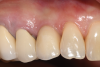

For infection control, the patient was placed on amoxicillin for the first week and told to rinse with a phenolic oral mouthrinse for the first 3 months. The patient was instructed to refrain from mechanical oral hygiene efforts for the first month. She underwent stringent postoperative management for the first year. Clinical examination 1 year postoperatively demonstrated that the 8 mm to 9 mm probing depths on the mesial and distal palate now measured 4 mm without bleeding (Figure 8), and a periapical radiograph suggested favorable bone gain (Figure 9).

Fig 8. Clinical buccal view at 1-year postoperative. Probing depths were now 3 mm with no bleeding.

Figure 8

Fig 9. Radiograph exposed at 1 year following the surgery suggested favorable bone gains achieved by eradicating the infraosseous lesions.

Figure 9